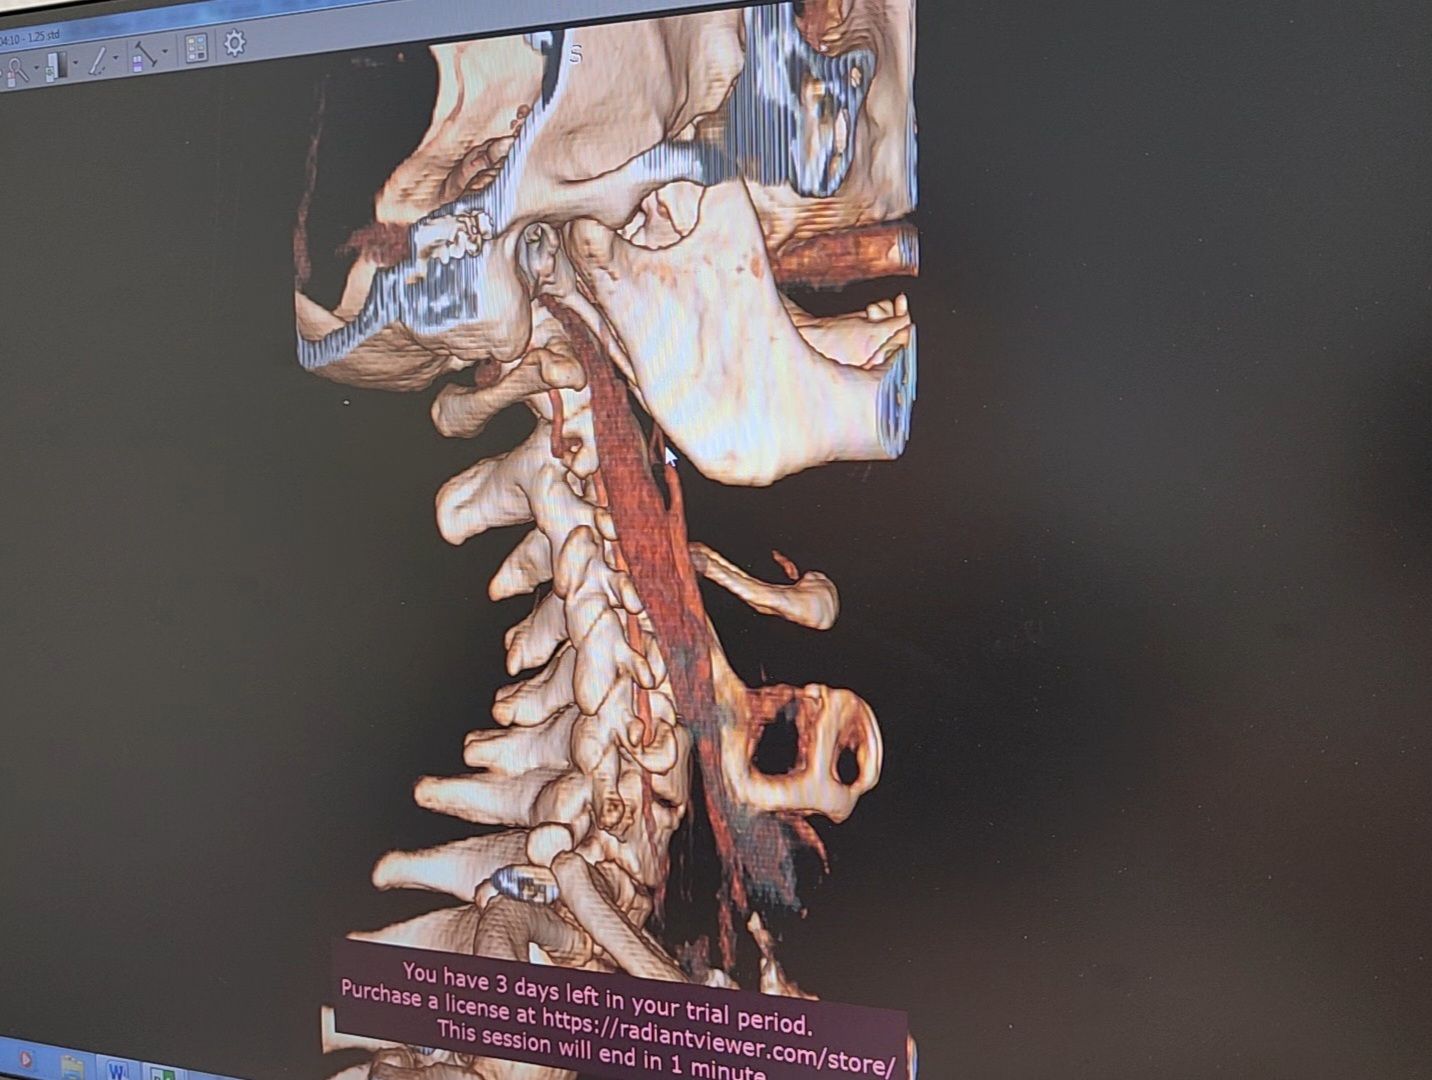

Изначально пациент обратился с жалобами на сердце. Бляшку в сонной артерии обнаружили с помощью компьютерной томографии. С пациентом работали группа врачей-хирургов, анестезиологов, кардиологов и неврологов. Операция прошла в штатном режиме. Пациент уже выписан на амбулаторное наблюдение и чувствует себя хорошо.